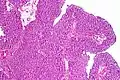

Histopathology of transitional carcinoma of the urinary bladder. Transurethral biopsy. Hematoxylin and eosin stain. | |

Transitional refers to the histological subtype of the cancerous cells as seen under a microscope.

The 1973 WHO grading system for transitional cell carcinomas (papilloma, G1, G2 or G3) is most commonly used despite being superseded by the 2004 WHO[14] grading for papillary types (papillary neoplasm of low malignant potential [PNLMP], low grade, and high grade papillary carcinoma). High-grade carcinoma typically displays more pleomorphism, multiple mitoses, euchromatin and relatively prominent nucleoli, and uneven distribution of nuclei.

- Transitional cell carcinoma, being low-grade to the left, and high-grade to the right. H&E stain

- Papillary transitional cell carcinoma, low grade

- Histopathology of urothelial carcinoma of the urinary bladder, showing a nested pattern of invasion. Transurethral biopsy. H&E stain

- Histopathology of urothelial carcinoma of the urinary bladder.

- Micrograph of urethral urothelial cell carcinoma. H&E stain